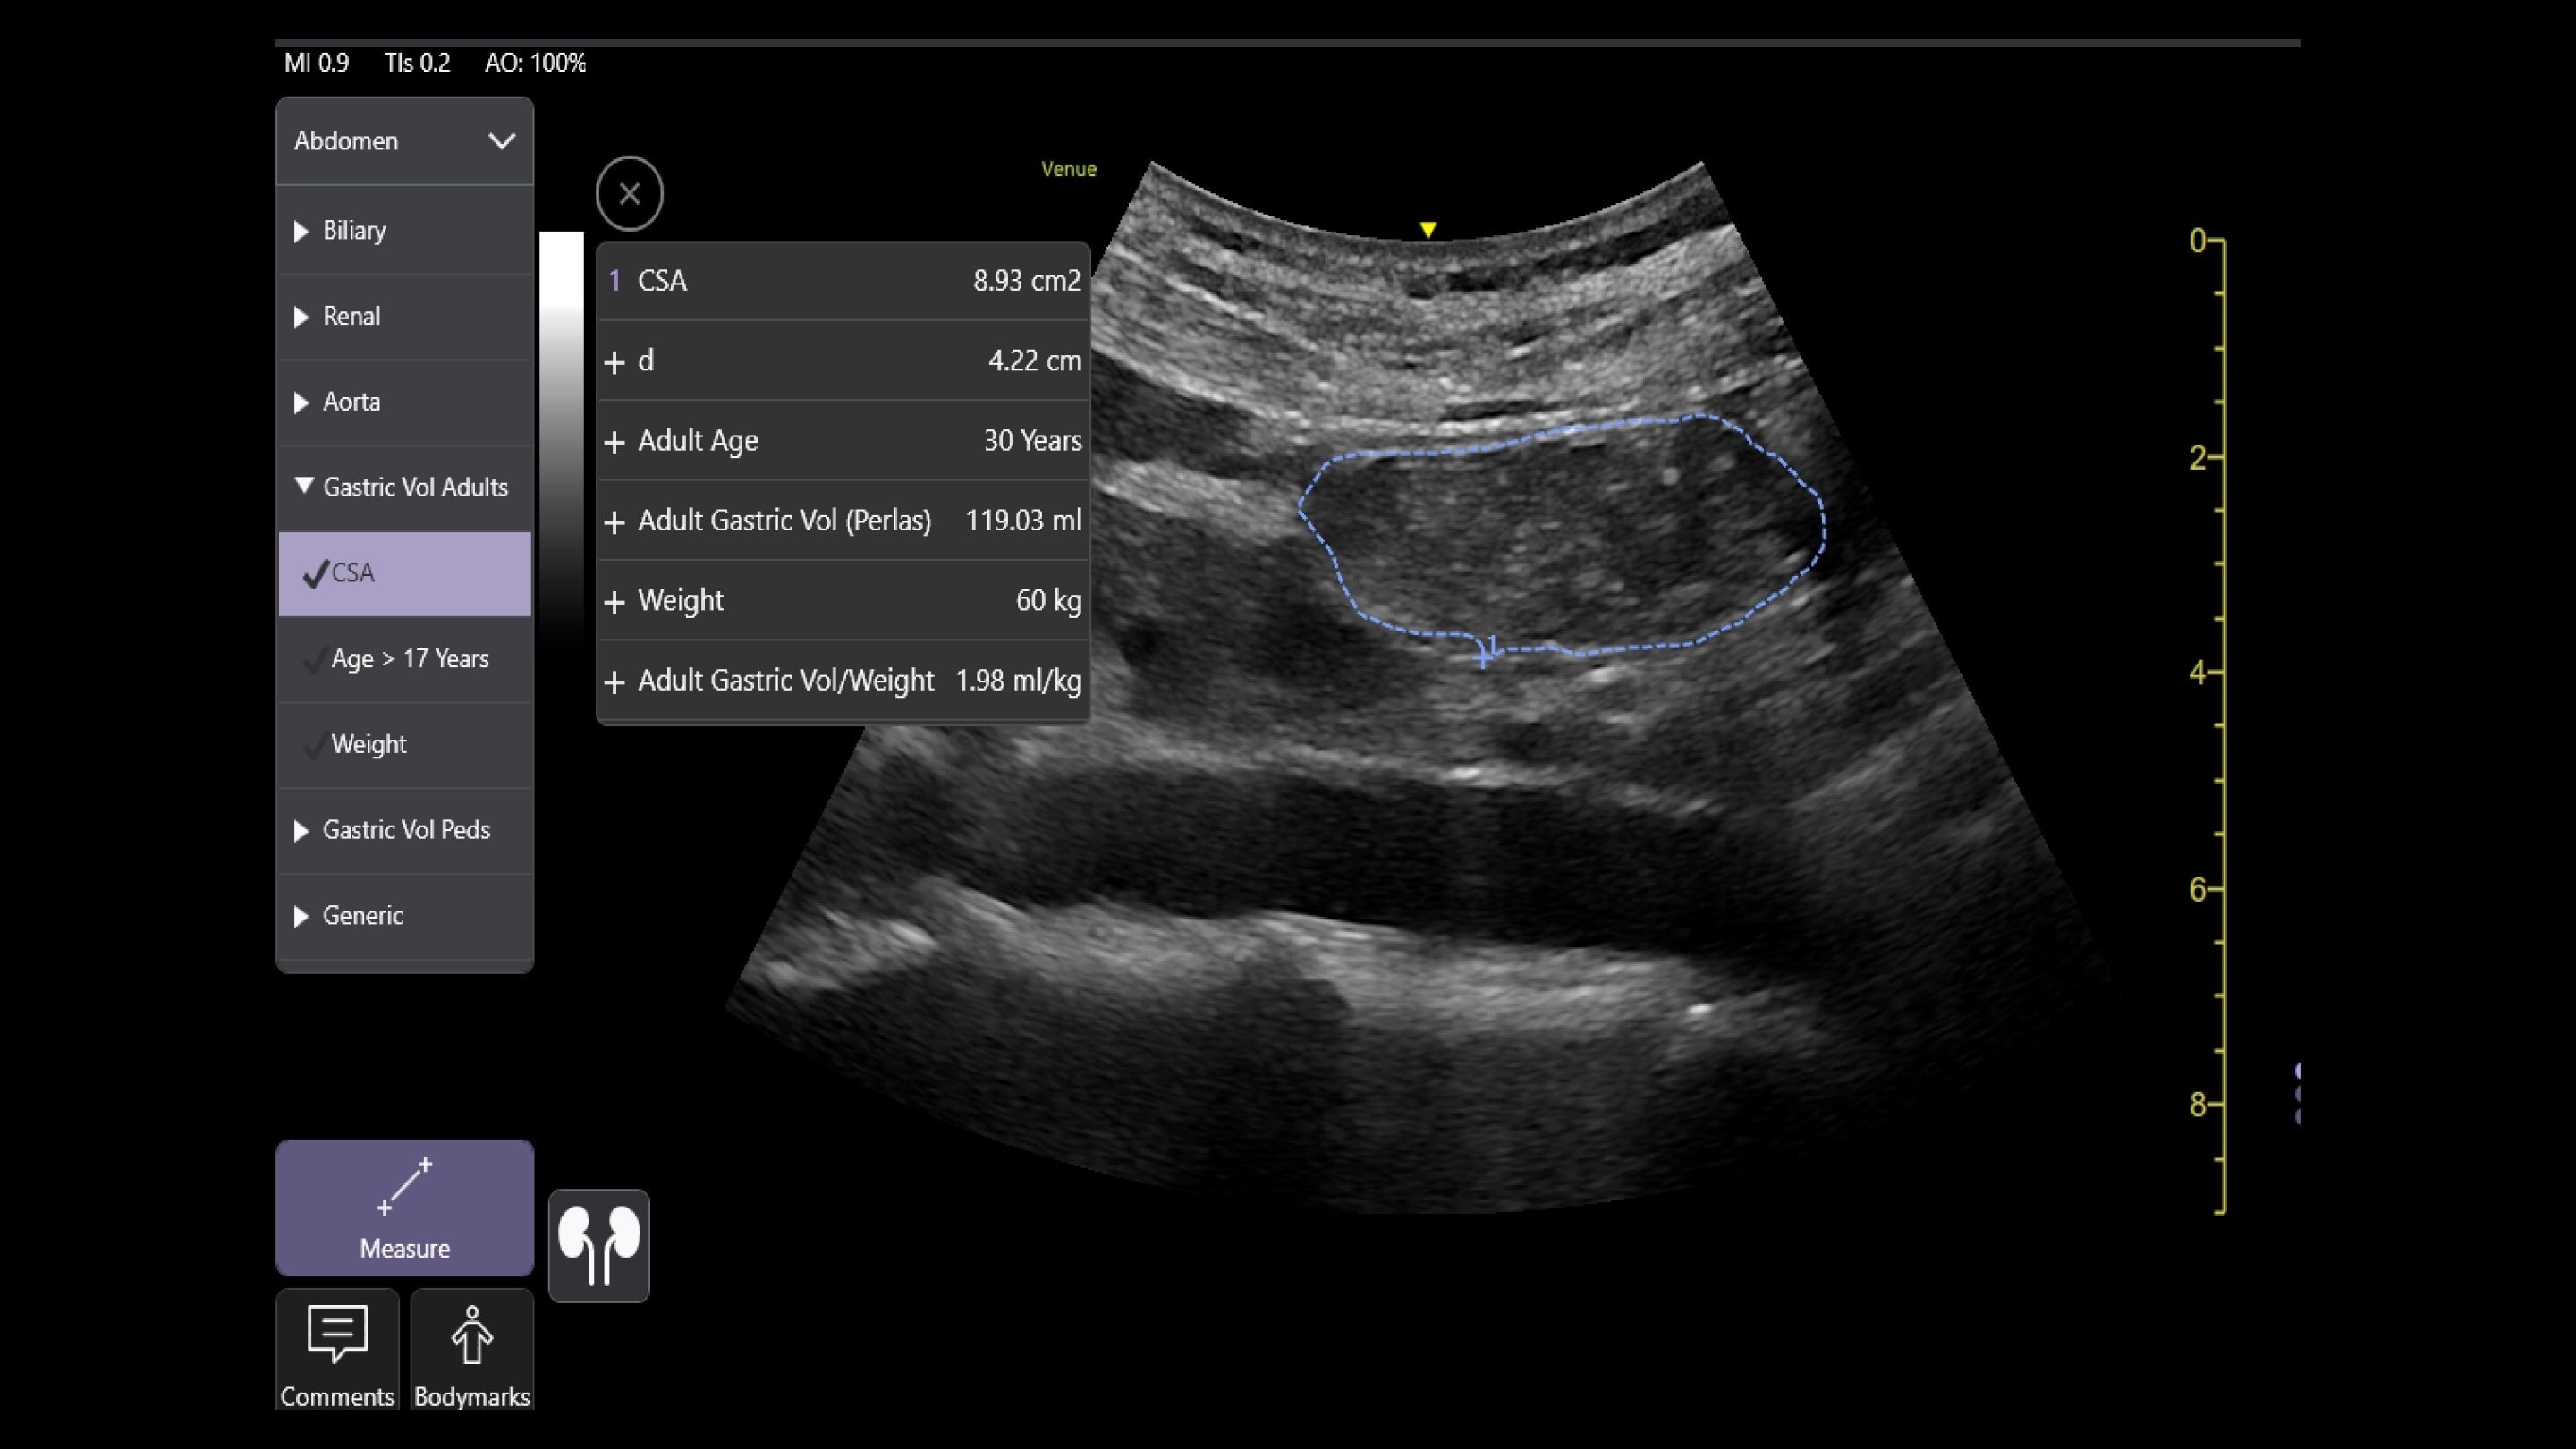

Venue Sprint™ gives you the uncompromised image quality and smart workflow of Venue™ family systems along with the freedom and maximum portability of wireless probes. This all-in-one, entry-level solution combines wireless connectivity with a small, streamlined console. It features Venue family software, to give you access to the AI tools you need, to simplify advanced exams whenever and wherever care is needed.

With the portability and mobility to go anywhere, you can get ahead with Venue Sprint. Take handheld ultrasound to different clinical spaces, sync up and be ready to go. Venue Sprint supports a wide range of environments including:

Enables on-the-spot visual confirmation, aiding the team in decision-making and collaboration on complex cases.